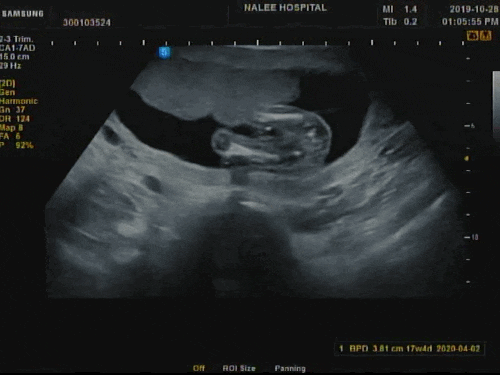

[17주] 2차 기형아 검사 & 성별 확인 , 임신 중기 영양제 : ‘딸엄마 되다’ ;D

2차 기형아 검사 받으러 가는 날이였어요 한 달에 한 번 가는 병원 날이 너무 기다려지는!! 입덧이 조금 끝...